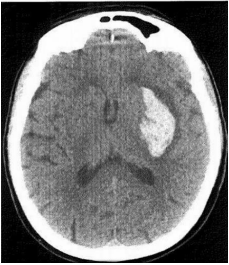

Mulher de 38 anos é levada à emergência após uso de cocaína. Apresenta-se com Glasgow 5, hipertensa e taquicárdica. Após intubação orotraqueal, foi realizado tomografia de crânio que mostrou imagem abaixo. Qual o diagnóstico?